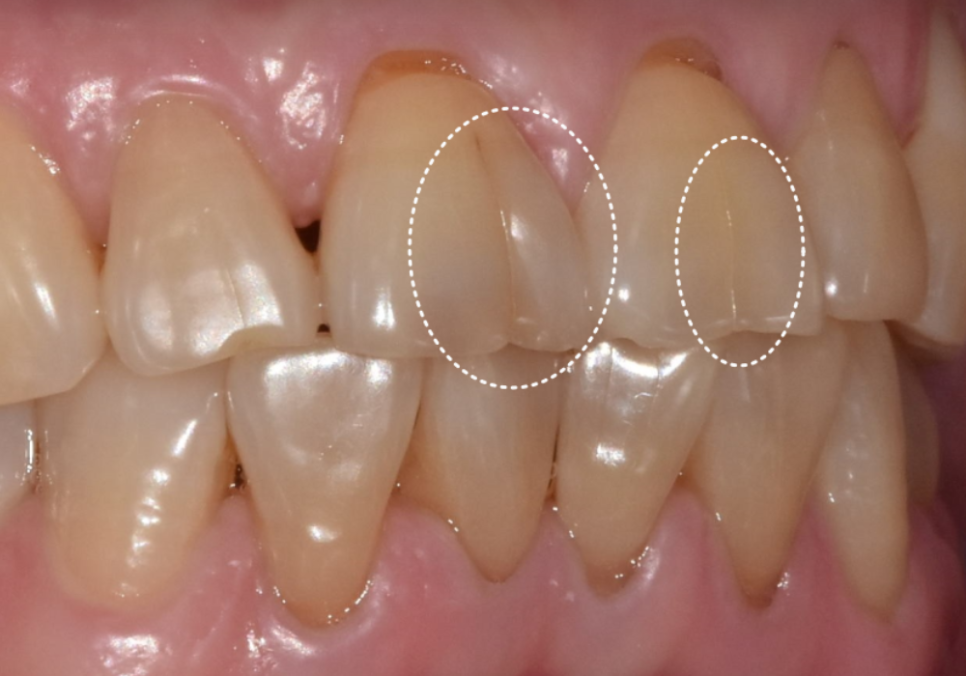

최근 저희 치과를 찾으신 환자분은

오른쪽 위 맨 끝 어금니(#17)가

씹을 때마다 너무 시큰거려서

식사가 힘들다고 하셨어요.

231221

겉으로 보기에는 큰 충치가 없어 보였지만,

자세히 살펴보니 씹는 면을

가로지르는 미세한 실금이 관찰되었습니다.